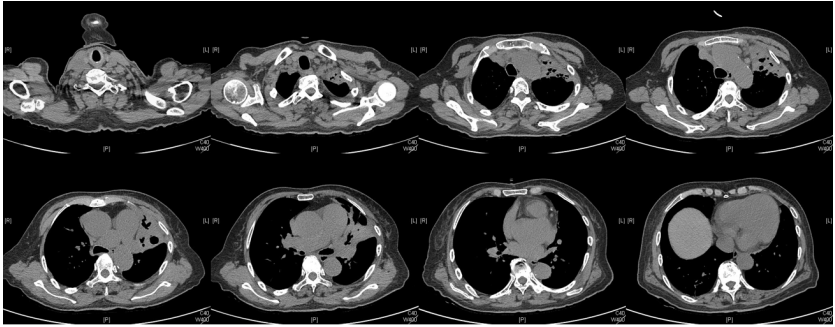

由于厌氧菌培养非常困难,既往我们对厌氧菌的认知仅限于在消化道定植,对其致病机制以及何种情况下致病并不非常清楚。厌氧菌定植于皮肤黏膜,是一种内源性微生物,感染发生率高,可导致严重、致死性感染。由于标本采集和转运的特殊性,使厌氧菌难以分离;加之其培养困难,体外生长慢,所以既往很难识别。厌氧菌在治疗方面存在一定挑战,如往往混合多重感染,且易产生耐药,也会因治疗延迟导致治疗失败。随着近10年来NGS技术的应用和普及,我们对厌氧菌的认识得以提升。常见的致病厌氧菌分为革兰阳性球菌、革兰阴性球菌、革兰阳性非芽孢杆菌、革兰阳性芽孢杆菌以及革兰阴性杆菌(表1)。革兰阳性非芽孢杆菌中可能致病的是放线菌,例如龋齿放线菌参与龋齿的发病过程。革兰阳性芽孢杆菌往往具有致病性,其中产气荚膜杆菌、艰难梭菌/难辨梭状芽孢杆菌、肉毒杆菌/肉毒梭菌、破伤风梭菌/杆菌具有强致病性。革兰阴性杆菌中的拟杆菌属对青霉素类药物具有很强的耐药性,易致青霉素治疗失败。临床中我们与厌氧菌的接触逐渐增多,对其特点也会愈发熟悉,对于临床诊断和治疗也会有所帮助。在NGS报告中通常会将检出的厌氧菌列为“C类”,定义为致病性C类—呼吸道正常微生态菌群,一般不导致感染。但当患者存在误吸风险时,需关注厌氧菌引起肺脓肿的可能。此时就需要针对患者的危险因素、临床表现、影像学、病原学以及气管镜下特点等进行综合分析。微小单胞菌最早是通过培养进行鉴定。瑞士2015—2022年132例病例报告的培养鉴定结果显示,血液中检出微小单胞菌37例(28%),肺内(肺脓肿、脓胸)检出29例(22%),总体病死率较低(5.3%)。国内周华教授团队开展的一项回顾性研究分析了2019年1月至2020年7月经病理活检和mNGS诊断的5例与微小单胞菌相关的慢性肺脓肿患者。患者的平均病程为6.5个月,共同特征是口腔卫生差,有酗酒史,且CT表现为边界不规则的高密度团块状实变影,并且在病灶中间可见液化性坏死,但没有发现气液平面或空腔,所以前期易被误诊为肺癌。下图1是该研究报告中病例3的肺部CT表现。时间点1:首次就诊时,左下叶可见团块状肺不张,伴周围磨玻璃样渗出病变,中心坏死不明显,可见细小空气囊泡影。时间点2:发病8个月时,可见大面积肺实变,增强CT示病灶内有液化坏死和小空洞。时间点3:经过3个月的有效抗厌氧菌治疗,病灶明显缩小,遗留空洞和纤维增殖病灶。图2是病例4的肺部CT表现。时间点1:患者首次就诊时,右上叶可见肿块样肺部实变影。时间点2:发病8个月时增强CT,可见实变明显增大,病灶内出现液化坏死。时间点3:经过3个月的有效治疗,病灶明显缩小,有残留空洞和纤维瘢痕样病变。由于通过影像学鉴别该病与肺癌具有挑战性,所以5例患者都接受了支气管镜检查和CT引导下经皮肺活检。5例患者经组织活检或支气管肺泡灌洗液(BALF)标本mNGS检测到微小单胞菌。病例: 女性, 67岁, 主诉"咳嗽咳痰2个月"。现病史:2个月前,患者家属感染新冠病毒(家属新冠抗原阳性)之后,患者出现咳嗽咳黄脓痰,无痰中带血及痰液拉丝,痰无臭味,无胸闷气短及胸痛,无咽痛咽痒,无鼻塞流涕。6月9日于当地市医院住院,住院期间出现发热,体温最高38.6℃,无寒战,查新冠病毒核酸阳性,予先诺特韦/利托那韦片口服治疗。查胸部CT见左肺上叶软组织影,左肺上叶炎症。诊断肺脓肿,予头孢唑肟联合莫西沙星,治疗后复查胸部CT(6月26日)病灶较6月9日明显吸收好转。6月14日气管镜检査见左肺上叶支气管开口狭窄,见大量脓性痰液堵塞支气管开口(病原学结果家属无法提供)。6月30日办理出院后仍有咳黄脓痰,无发热畏寒,口服止咳化痰药物,未使用抗生素。7月30日复诊胸部CT见左肺上叶异常密度较前增大。8月2日再次于当地市人民医院住院。8月4日气管镜检查: 左肺上叶黏膜肿胀肥厚, 管腔狭窄, 见大量白色干酪样分泌物涌出, 支气管镜不能进入。内科予莫西沙星静滴治疗10天, 外科予莫西沙星联合哌拉西林他唑巴坦静滴9天。复查胸部CT见病灶较前进展, 且右肺出现新发感染病灶。病程中患者饮食可, 睡眠差, 二便正常, 体重减轻5 kg。既往对阿莫西林过敏, 表现为口服阿莫西林后全身皮疹。否认嗜酒史及吸烟史。入院后胸部增强CT可见病灶内液化坏死,同时伴有小的空气囊泡影(图3)。患者有胸痛症状。气管镜检查发现气道内有痰栓或黏液栓阻塞征象(图4)。灌洗液tNGS结果回示:微小单胞菌(序列数2762),巨细胞病毒(序列数171),副流感病毒(序列数79),EB病毒(序列数61)。考虑病毒不会导致气道内如此改变,但由于微小单胞菌属于常见口腔定植菌,此时也不能完全确定微小单胞菌是否为引起感染的主要责任病原体。8月24日起予莫西沙星0.4 g qd ivgtt+哌拉西林他唑巴坦4.5 g q8h ivgtt。经过上述治疗,患者局部病灶有所吸收,但整个肺叶并无明显改善(图5)。气管镜检查仍然发现气道内有较黏稠的黏液栓阻塞气道开口(图6)。治疗经过:气管镜下予以局部冲洗,再次送检tNGS。9月7日结果回示:微小单胞菌(序列数6464),较前明显增多;副流感病毒(序列数998),EB病毒(序列数331)。9月9日起调整治疗方案为美罗培南1 g q8h。9月12日复查患者胸部CT,可见肺通气部分改善,肺组织内实变较前吸收(图7)。第三次气管镜检查仍可见少量痰栓嵌塞在远端支气管开口(图8)。患者此后转入医联体医院继续抗感染治疗。病例2:女性,54岁。主诉:咳嗽咳痰2个月,发热1周。现病史:入院2个月前,患者在西南地区旅游时感冒,出现咳嗽咳痰,白痰为主,量多,无胸痛,无发热,无痰中带血,咳时气短。于河北某诊所间断输液治疗14天(具体不详),期间口服中药治疗,症状未缓解。入院3周前(2023-09-07)就诊于当地县医院,查胸部CT提示右肺炎症,静脉滴注氨曲南、左氧氟沙星、氨溴索治疗1周,症状未缓解。2023年9月14日复查胸部CT显示右肺炎症较前加重,于当地中心医院住院。动脉血气分析:pH 7.43,PaCO2 38.4 mmHg,PaO2 67 mmHg,SaO2 94.2%;血沉90 mm/h;生化:白蛋白35.3 g/L;CRP 82.7 mg/L;血常规:WBC 9.75×109/L,NEU 6.83×109/L,HGB 104 g/L。静脉滴注莫西沙星。入院10天前,行肺穿刺活检,病理回报为少量肺组织及纤维结缔组织,炭末沉积,较多中性白粒细胞、淋巴细胞及浆细胞浸润,伴脓肿形成;肺穿刺mNGS结果回报:微小单孢菌(序列数2650),鲍曼不动杆菌(序列数17),人类疱疹病毒4型(序列数60),人类疱疹病毒7型(序列数5),文氏密螺旋体(序列数4337),解卵磷脂密螺旋体(序列数1121),齿垢密螺旋体(序列数698)。调整抗生素为头孢哌酮舒巴坦2 g q12h。入院1周前,出现发热,体温最高38.5℃,不伴寒战,咳嗽咳痰无加重,无咯血;复查血常规、PCT、CRP均明显增高(未见报告单);复查胸部X线提示右肺炎症范围增大,右侧胸腔积液。更换抗生素为哌拉西林他唑巴坦4.5 g q8h。4天前,支气管镜下见右肺下叶背段支气管略狭窄,黏膜水肿,可见脓性分泌物溢出。BALF革兰染色查见革兰阴性杆菌,抗酸染色、霉菌未见异常,培养未回报。患者体温逐渐降至正常,咳嗽咳痰有所减轻,复查胸部CT提示右肺高密度影,右侧胸腔积液较前增多。为求进一步诊治来我院就诊被收入院。既往甲状腺功能减退病史5年,目前口服优甲乐治疗,监测甲状腺功能指标在正常范围。20年前因宫外孕行手术治疗。2023年10月8日胸部CT示胸膜下斑片状坏死,纵隔窗可见微小空气囊泡影及密度不均匀液化坏死(图9)。治疗:9月28日至10月13日莫西沙星0.4 g qd ivgtt+哌拉西林他唑巴坦钠4.5 g q8h ivgtt。最终患者病灶吸收好转并顺利出院。患者男性,42岁。主因间断咳嗽、咳痰1月余,左侧胸痛、气短2天入院。现病史:入院前1月余(2022-07-19),患者无明显诱因出现咳嗽,咳白痰,痰中有少量鲜红色血丝,左侧胸痛(为钝痛),深吸气后加重,就诊于当地医院。完善肺动脉CTPA:示左上肺动脉舌段分支局部管腔可见线条样低密度充盈缺损,考虑肺栓塞;左肺上叶实性病变伴不均匀强化,性质待定,部分为肺梗死改变可能,纵隔多发稍大淋巴结,性质待定;右肺下叶后基底段可见一不规则实性结节,边缘可见多发毛刺,直径约0.7 cm。当地医院考虑肺栓塞不除外,肺部感染?右肺下叶结节,予莫西沙星抗感染,低分子肝素抗凝,乙酰半胱氨酸化痰。完善CT引导下肺穿刺活检,病理示:肺泡腔扩张伴上皮轻度增生,肺泡间隔纤维组织增生伴散在炎细胞浸润,未见恶性病变。院外规律应用甲磺酸艾多沙班60 mg bid抗凝,先后间断应用左氧氟沙星0.5 g qd、头孢类抗生素(具体药物、剂量不详)抗感染。患者仍有间渐咳黄白痰,量不多,痰中有少量鲜红色血丝;无畏寒、发热、胸痛、夜间阵发性呼吸困难症状,无尿少、双下肢水肿,无口干、咽干,无牙齿成片脱落,无晨僵、关节肿痛,周身无皮疹,无盗汗乏力。2天前(2022-09-16)患者无明显诱因再次出现左侧胸痛,疼痛剧烈,深吸气、咳嗽及改变体位时加重,伴气短,就诊于我院急诊。完善肺动脉CTPA:肺动脉主干及其各叶段分支未见明显充盈缺损,左肺上叶舌段团块影,最大截面约7.6 cm×5.3 cm,边界不清,周围可见晕征;增强扫描不均匀强化,邻近胸膜增厚,性质待定,建议穿刺活检;纵隔及左肺门多发淋巴结显影。血细胞分析:WBC 11.09×109/L,NEU% 80.8%,NEU 8.95×109/L;CRP 54 mg/L,PCT 0.07 ng/ml。患者自发病以来,精神状、食欲及睡眠均一般,大小便正常,体重下降5 kg。2022年9月14日外院胸部增强CT:胸膜下楔形的影像学表现可见少量小气泡囊以及液化坏死病灶(图10)。初始考虑肺部肿瘤及肺栓塞。经过初步抗感染及抗凝治疗,患者病情无缓解,2022年9月27日患者突发胸痛,下肺影像加重并且出现脓胸(图11)。行胸腔穿刺并将脓液送检mNGS,结果回报:牙龈卟啉单胞菌(序列数3)。尽管序列数很低,但考虑是脓肿穿刺结果,因此考虑该菌致病可能。抗厌氧菌治疗:9月16-28日莫西沙星0.4 g qd ivgtt,9月23日-10月12日美罗培南1 g q12h ivgtt,9月28日-10月8日万古霉素1 g q12h ivgtt,10月13-18日莫西沙星0.4 g qd ivgtt+甲硝唑0.5 g tid ivgtt。患者肺脓肿的整体治疗时间约为3个月,病灶逐渐吸收,最终形成一些纤维索条影(图12,图13)。1年后复查病灶基本吸收(图14)。图14 1年后复查胸部CT(2023-08-08)微小单胞菌和卟啉单胞菌这两种厌氧菌在临床中需要引起重视,它们容易引起肺脓肿/脓胸。2024年国内学者Li Yao等在Diagn Microbiol Infect Dis 杂志发表了一篇牙髓卟啉单胞菌感染所致肺脓肿的病例报告,文章也提到在胸水或肺组织活检中,通过mNGS同时检出了微小单胞菌和卟啉单胞菌感染引起的肺脓肿。文章还回顾总结了既往发表的厌氧菌感染引起肺脓肿的病例,2010年报道的是1例脑脓肿患者,2019年报道1例脑炎患者,2022年报道1例脓胸伴呼吸衰竭患者。3例患者预后都比较好,可见厌氧菌亦可导致肺外多部位感染。对于厌氧菌所致肺脓肿的诊断及其引起的脓胸,目前的文献报道仍然较少,我们对它们的认知也有限,因此也提醒大家关注相关疾病的诊断和治疗。我们也已将本研究小组8例微小单胞菌所致肺脓肿的系列病例的研究结果发表(Front Cell Infect Microbiol, 2024, 14: 1416884),可供需要的同行参考。对于厌氧菌感染,我们需要提高警惕。厌氧菌往往在口咽部定植,其引起的脓肿/感染往往多为亚急性或慢性起病。患者通常有发热、胸痛症状,脓肿会逐渐进展。由于厌氧菌与人体本身是一种长期共生的关系,人体对厌氧菌的免疫识别可能处于较低的防御反应状态,所以会形成一个亚急性或慢性的发病过程。通常情况下,因厌氧菌的菌群发生了移位,从卫生条件不好的口腔扩展到相对无菌的肺内,同时开始增殖,由此可能导致感染。因此,对于酗酒以及口腔卫生非常差的人群,我们要重视对其风险因素和病史的排查。患者就诊时可能病情并不重,有胸痛或咯血,很容易误诊为肺部肿瘤,往往在这种情况下进行肺穿刺或气管镜检查,mNGS可以发现较大序列数的厌氧菌。但在mNGS检出厌氧菌后的诊断过程中又容易形成误判——究竟是致病菌,还是定植菌?此时结合患者其他病史和影像学特点(有脓肿/痰栓形成,微小空气气囊泡影),可能提示厌氧菌感染。然而,厌氧菌感染在病原学和影像学诊断方面仍然存在诸多困难,极易漏诊和误诊。微小单胞菌感染患者在气管镜下可以看到典型的脓性分泌物嵌塞气道,导致气道阻塞,也会造成远端气道和肺泡引流障碍。所以,及时处理气道内痰栓,改善引流,可能是使患者获得良好预后的关键。厌氧菌肺脓肿的吸收比较缓慢,抗感染的疗程也比较长,需要在后期诊疗过程中密切随访和观察患者对治疗的反应以及耐药等问题,及时调整治疗方案,适当延长疗程。